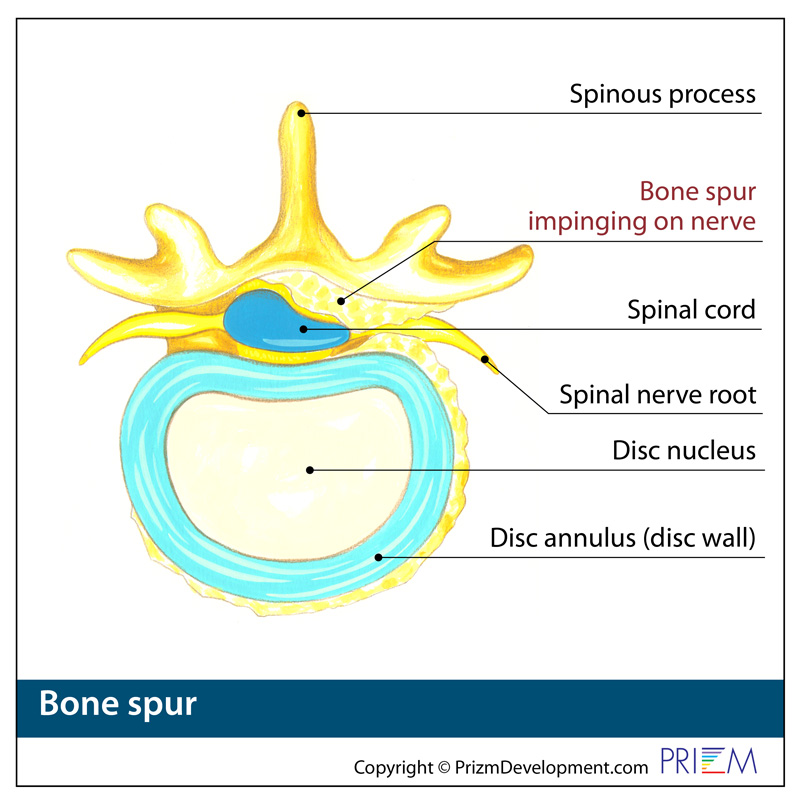

Thoracic Bone Spurs and Nerve Impingement – Request Physical Therapy

Arthritis (Spine) And Bone Spurs

Foraminal Stenosis of the Spine | Bone Spur | Dr. Donald Corenman …